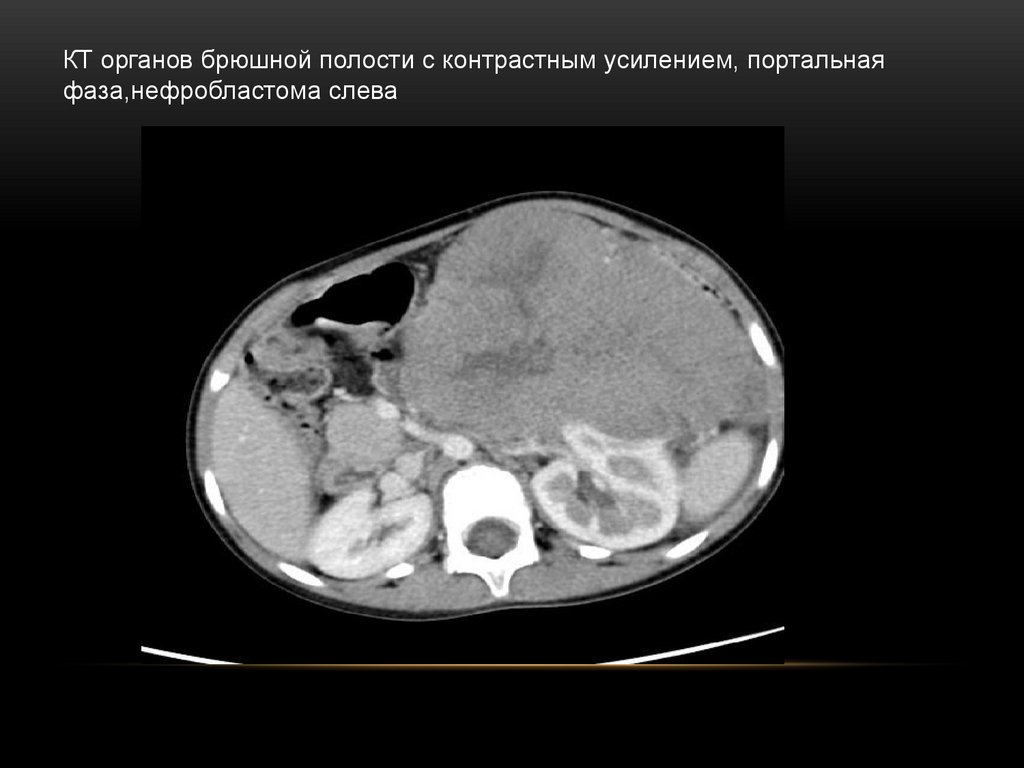

50.

КТ органов брюшной полости с контрастным усилением, портальная

фаза,нефробластома слева